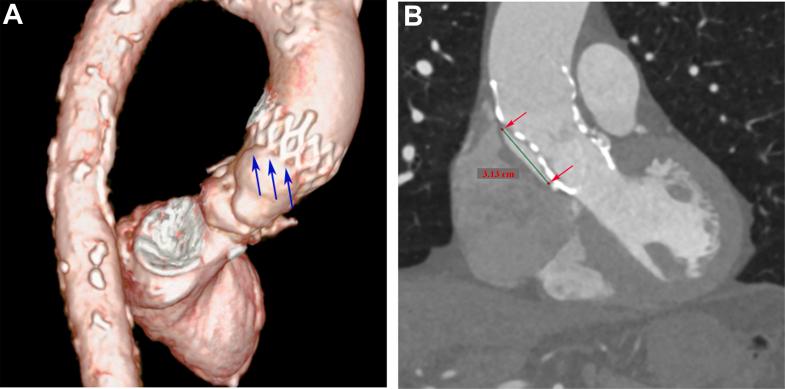

An older man with severe aortic stenosis underwent TAVR. During valve deployment, catheter manipulation caused intimal disruption, leading to acute type A aortic dissection (TAAD). Remarkably, the dissection spontaneously sealed after prosthetic valve placement, thereby avoiding emergency surgery. A 6-month follow-up computed tomography angiography scan showed no extension of the dissection.

In the case we report, the dissection spontaneously sealed with the use of a prosthetic valve, a finding that reinforces the feasibility of nonsurgical management of iatrogenic TAAD during TAVR in select cases.